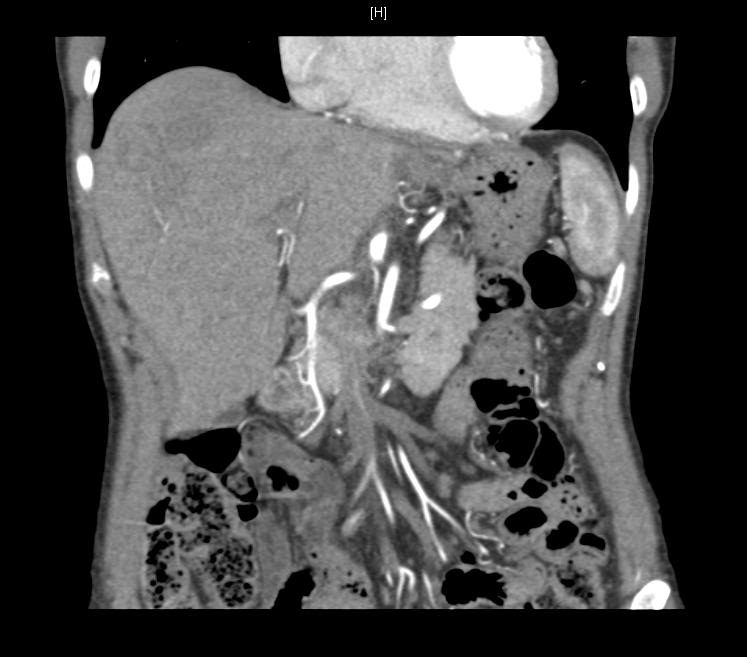

CT扫描显示肝叶转移和肺小结节病灶

CT scan pre-and 3 months post-RE

PET scan pre-and 3 months post-RE

CT scan 3 months post-hepatectomy